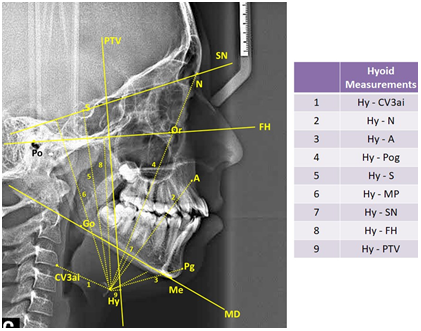

In study, 35 cephalometric points (Figure 1), 8 cephalometric planes, and 30 cephalometric measurements (Figure 2) were used. In the cephalometric analysis; 5 craniofacial, 8 nasopharyngeal, 7 oropharyngeal, 2 hypopharyngeal (Figure 3), 9 hyoid measurements (Figure 4) and 4 area measurements (Figure 5) were used.